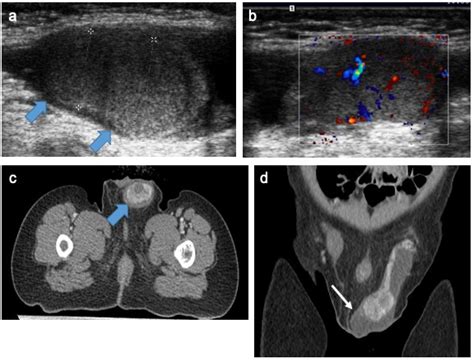

Diagnosing a testicular cyst typically involves a combination of the following:

• Physical Examination: A healthcare provider will perform a physical exam to feel for any lumps or abnormalities.

• Ultrasound: An ultrasound of the scrotum can help visualize the cyst and determine its size and location.

Diagnosis

Diagnosing testicular cancer involves several steps:

• Ultrasound: An ultrasound of the scrotum can help visualize the tumor and determine its size and location.